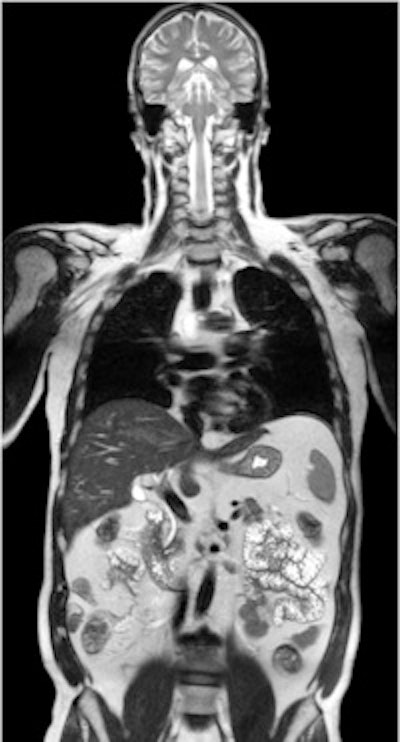

Left: PET tracer uptake in the liver can be combined with the time-varying enhancement of dynamic MR scans to visualize hepatic tumor characteristics. Right: MR and PET come together to support tumor staging. In this case, high-resolution MR provides a clear image of the pathology within the pelvic structure, while PET displays the hypermetabolism component of the lesion. Images courtesy of Siemens.Drzezga believes that combining the two modalities offers a number of clinical advantages, not least in eliminating the need for separate diagnostic examinations. Furthermore, the exact anatomical registration of structural and functional/molecular information may improve allocation of suspect findings and improve image quality, for example by motion correction of regions of the body that do not remain rigid during examination. The Munich team will also be exploring how the performance of PET/MR compares with that of PET/CT. There is some evidence that the superior soft-tissue contrast achievable with the newer system will offer significant benefits, even before physicians consider the safety issues involved with any radiation-based imaging technology such as PET/CT, Drzezga suggested.

Left: To improve the precision of spatial registration, the Biograph mMR system collects MR and PET data simultaneously from a single frame of reference. The result is a combined MR and PET scan acquired at the same point in time and reflecting the same point in the physiologic processes such as respiration. Right: The benefits of MRI in the study of neurological diseases are well-known and established, and it can lead to a better understanding of neurological pathologies. Images courtesy of Siemens.Philips has been working on its latest MR technology for almost as long as the search for a practical PET/MR hybrid. After an eight-year development project, the company is promoting its Ingenia 1.5- and 3-tesla systems, which it describes as the world's first digital broadband MR unit. This incorporates dStream architecture, which digitizes the signal directly in the coil. Vendors have been looking for ways to shorten the analogue part of the signal processing pathway because this offers the potential for reducing signal loss and noise. The Philips approach goes further by digitizing the signal within the coil itself and transporting it via a fiber-optic cable to the acquisition electronics contained in the scanner cabinet, explained Maurits Wolleswinkel, global lead for MR marketing.